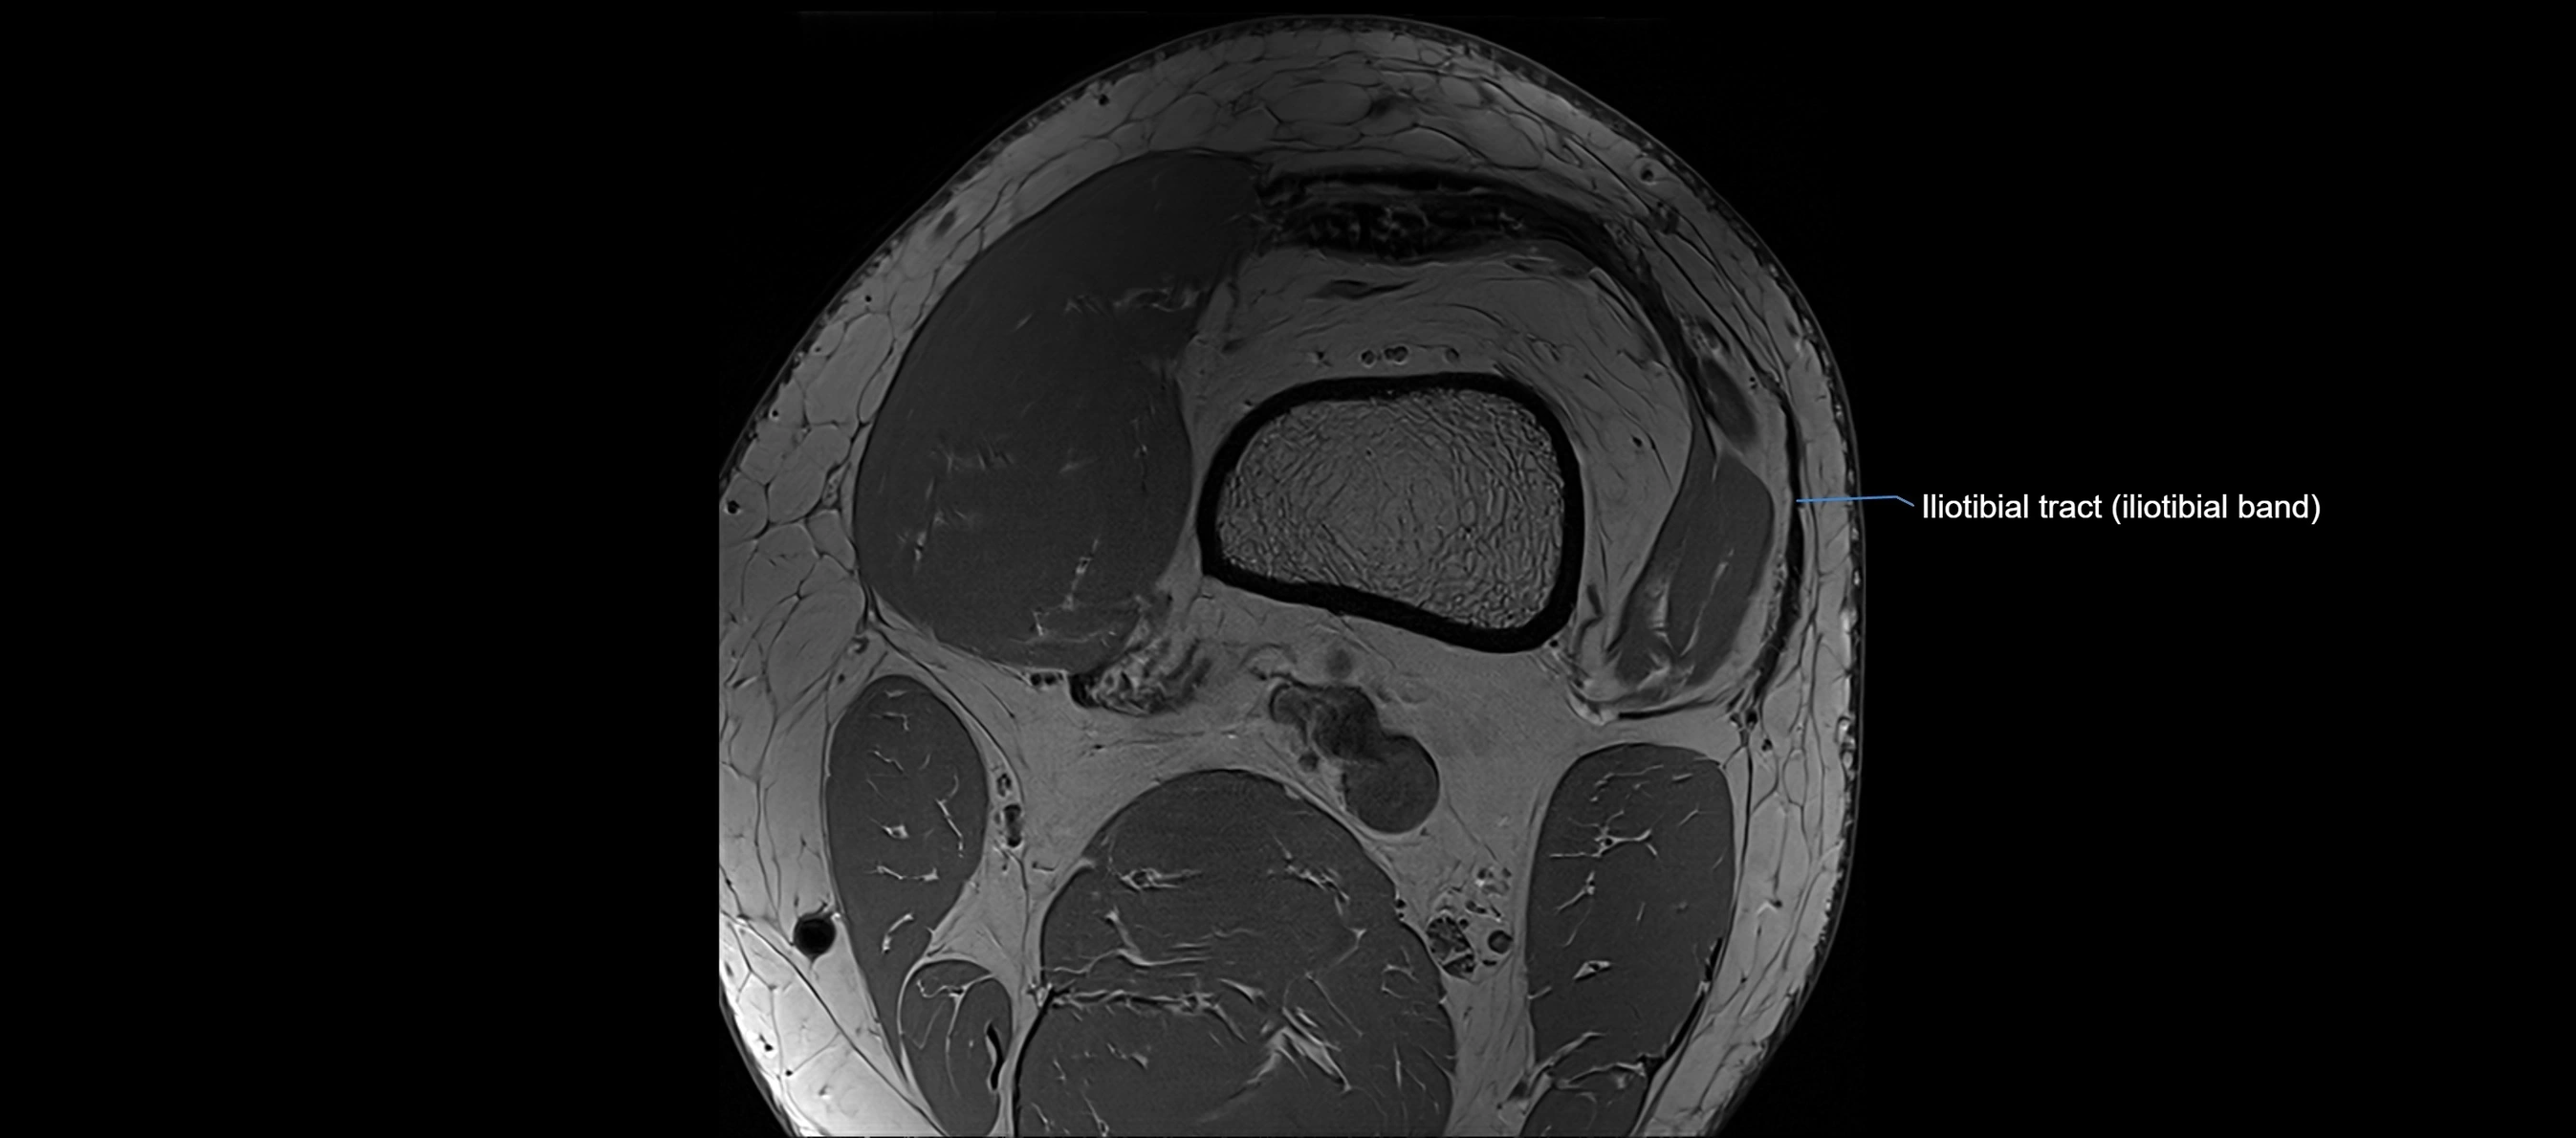

MRI images

image